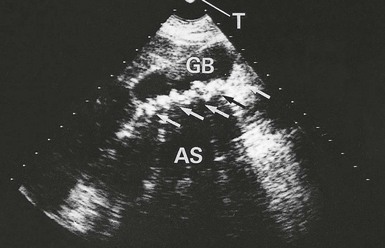

Imaging in investigating gall bladder pathology: Ultrasonography (see Fig. 20.4) can reliably identify stones in the gall bladder and any increase in thickness of the wall (caused by inflammation or fibrosis). Ultrasound also provides a simple and accurate means of demonstrating dilatation of the common duct system, often indicating distal duct obstruction. Unfortunately, it is unreliable for directly identifying bile duct stones, particularly at the lower end, because the image tends to be obscured by overlying duodenal gas. Ultrasound has the great advantage of being suitable for use in the seriously ill or jaundiced patient as it is non-invasive and can be performed at the bedside.

Fig. 20.4 Biliary ultrasound scans

Longitudinal scan of gall bladder in a 46-year-old woman who complained of intermittent attacks of right upper quadrant pain. The scan shows the outline of the gall bladder GB and a layer of gallstones (arrowed) along its posterior wall. The stones each cast a clear acoustic shadow AS beyond them. Note that these shadows can be projected back to the transducer T